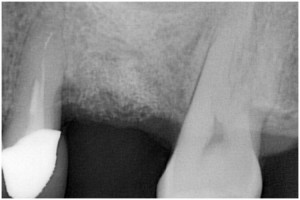

術前

同拡大

抜歯後

抜歯後GBR

GBR後

同拡大像